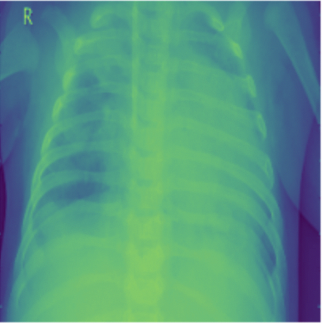

Pneumonia is an acute pulmonary infection which causes inflammation of air sacs called Alveoli. It is most common in underdeveloped or developing nations which have below average air quality and sanitation standards. Pneumonia can be of these three forms viral, bacterial or fungal which makes it airborne and contagious. It mostly effects children under the age of five or elderly people who have weak immune system [2]. Symptoms include coughing, fever, difficulty in breathing, loss of appetite etc. and is life threatening. COVID-19 induced Pneumonia has been a major reason for pandemic deaths in the world [3]. Pneumonia is a rapid attacking infection whose quick diagnosis is important for saving lives. Detection of Pneumonia normally requires a highly skilled doctor to look at the Chest X-rays (CXR) and CT scans and requires medical history to arrive at a conclusion. Normally a foggy CXR with white spots are a few indicators of Pneumonia Fig. 1. This manual process might be expensive and critically time consuming. The recent advancements in Machine learning and Computer vision might prove really helpful in quick and accurate detection of Pneumonia and can potentially save a lot more lives especially during pandemics like COVID-19 which faced shortage of human expertise.